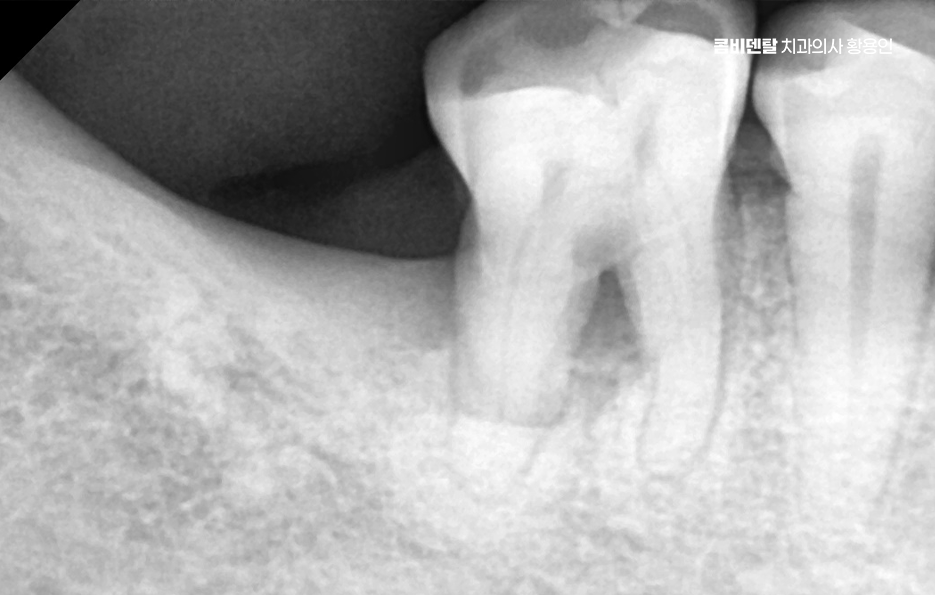

어금니 임플란트 과정은 정밀 진단에서 시작되며 잇몸뼈 안에 인공 치근을 심는 방식이기 때문에 뼈 상태 확인이 필수적으로 파노라마 촬영이나 3차원 CT를 통해 뼈 높이와 폭, 신경 위치를 확인하고 특히 아래 어금니는 하치조신경과 가까워서 정확한 위치 파악이 중요하며 위 어금니는 상악동과의 거리도 고려해야 할 필요가 있어요

임플란트를 심을 잇몸 뼈가 충분하다면 바로 식립이 가능하지만 치아를 빼고 오래 방치한 경우에는 뼈가 흡수되어 부족할 수 있으며 이때는 뼈이식을 먼저 하거나 동시에 진행하고 어금니는 씹는 힘이 강하기 때문에 초기 고정이 단단해야 하며 유지까지 고려할 때 교합의 정교한 맞물림이 중요한 부위라고 할 수 있었어요